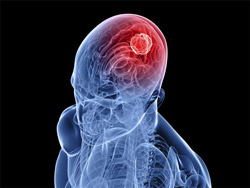

علائم تومور مغزی

یک متخصص مغز و اعصاب گفت: تومور مغزی به صورت یک توده بروز میکند؛ این بیماری با بالا رفتن فشار درون مغز خود را نشان میدهد و سردرد، تهوع، سرگیجه، تاری دید، تشنج، کما و اغما از علائم افزایش فشار درون مغز است.

یک متخصص مغز و اعصاب گفت: تومور مغزی به صورت یک توده بروز میکند؛ این بیماری با بالا رفتن فشار درون مغز خود را نشان میدهد و سردرد، تهوع، سرگیجه، تاری دید، تشنج، کما و اغما از علائم افزایش فشار درون مغز است. دکتر علیاکبر مومن اظهار کرد: بروز این علائم به نوع تومور بستگی دارد، بسته به این که تومور بدخیم باشد یا خوشخیم، علائم شدت و ضعف خواهند داشت و به اندازه بالا رفتن فشار داخل جمجمه متغیر خواهند بود.

مومن با اشاره به دلایل بروز و درمان تومور مغزی افزود: تومور مغزی مانند هر سرطان دیگری دلیل مشخص و معلومی ندارد؛ بنابراین نمیتوان راه دقیقی برای پیشگیری از ابتلا به آن معرفی کرد، تنها میتوان گفت که سبک زندگی، مصرف غذاها و شرایط محیط زندگی میتوانند در سلامت مغز تاثیرگذار باشند.

وی با بیان این که ایجاد تومور مغزی در تمام سنین شیوع دارد، گفت: در تمام سرطانها از جمله سرطان مغز، راه درمان به نوع تومور بستگی دارد و این که تومور در کدام قسمت باشد. معمولا جراحی، درمان اصلی تومور مغزی است؛ اگر تومور قابل برداشت باشد و جراحی به قسمتهای دیگر مغز آسیب نرساند، جراح مغز و اعصاب تومور را برمیدارد.

این متخصص مغز و اعصاب اظهار کرد: در برخی موارد به دلیل فشاری که تومور ایجاد میکند، آب درون مغز جمع میشود و باید راهی را از مغز به بیرون باز کرد و آن را تخلیه کرد. در چنین شرایطی، معمولا راهی به درون شکم باز میکنند تا بتوانند فشار مایع زیاد درون مغز را تخلیه کنند. علاوه بر درمان با جراحی، از شیمیدرمانی و رادیوتراپی نیز در درمان تومورهای مغزی استفاده میشود.

مومن افزود: تومورها علاوه بر این که به خوشخیم و بدخیم تقسیمبندی میشوند، بنا به این که تومور در چه قسمتی از مغز باشد، نامگذاری میشود و علائم آنها نیز متفاوت است؛ تومورهای نخاع یا قسمتهای تحتانی و فوقانی مغز علائم متفاوتی دارند.

وی گفت: این که یک تومور مغزی در چه مدت زمانی انسان را از پای درآورد به نوع تومور و محل آن بستگی دارد. اگر تومور نزدیک به محلهای حیاتی مغز مانند ساقه مغز و حفره خلفی مغز قرار داشته باشد، در صورتی که درمان نشود، بیمار را به سرعت از پای در میآورد.

این متخصص مغز و اعصاب درباره چگونگی بروز علائم این بیماری گفت: مدت زمان و چگونگی بروز علائم به محل قرارگیری تومور بستگی دارد؛ اگر تومور در فضاهای محدود مغز باشد، زودتر خود را نشان میدهد. مثلا تومورهای حفره خلفی مغز خود را سریعتر نشان میدهند. اما اگر تومور در قسمتهایی از مغز باشد که فضای وسیعتری دارند، ممکن است مدتی طول بکشد تا علائم آن بروز کند؛ تومورهایی که در نیمکرههای مغز هستند ممکن است مقداری طول بکشد تا خود را نشان دهند.